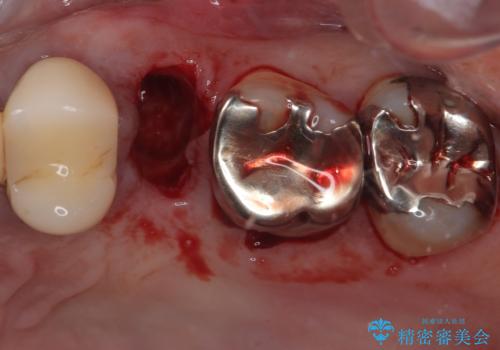

- 今回ご紹介するのは、左上の小臼歯(第二小臼歯)の治療を希望されて来院された患者様です。

診査の結果、該当歯は**虫歯が歯肉の奥深くまで進行し、根だけが残っている状態**でした。

このようなケースでは、歯を残すことが難しく、従来なら抜歯後に一定の治癒期間をおいてからインプラント治療を行うのが一般的です。

今回は、外科処置の回数を減らし、患者様の負担を最小限にするため、

**抜歯と同時にインプラントを埋入する「抜歯即時インプラント」**を選択しました。

抜歯と同時にインプラントを埋入し、その日のうちに仮歯を装着。

即日で審美性を回復できたため、治療当日から自然な見た目でお過ごしいただけました。